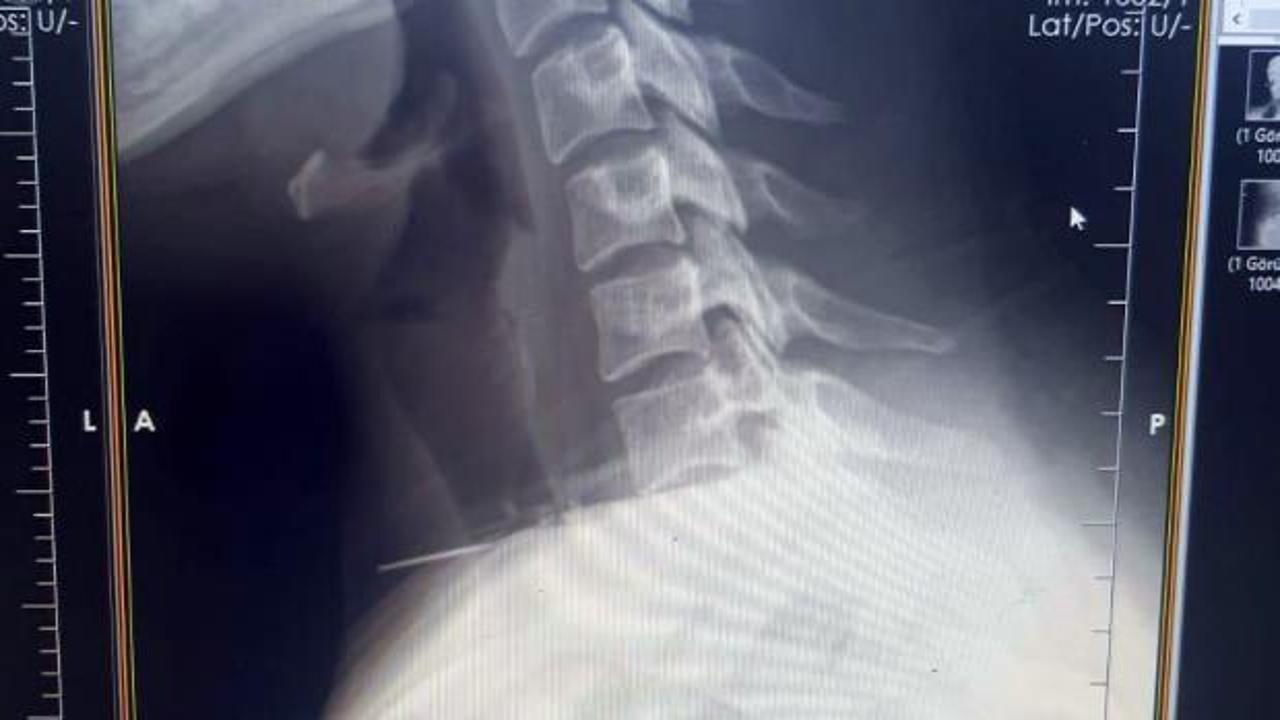

İl Sağlık Müdürlüğünden yapılan açıklamaya göre, başörtüsünü takarken boğazına iğne saplanan 25 yaşındaki Z.İ, Birecik Devlet Hastanesine başvurdu. Yapılan radyolojik incelemeler ve klinik değerlendirmeler sonucunda, 3 santimetrelik iğnenin boğaz bölgesinin derinliklerine doğru ilerlediği tespit edildi.

Yaklaşık 1 saat süren ameliyatla iğne çıkarıldı ve hasta ameliyat sonrası süreci sorunsuz atlatıp taburcu edildi. Ameliyatı gerçekleştiren Dr. Rafet Yıldırım, bu tür vakaların nadir görüldüğünü belirterek, dikkatli olunması gerektiği konusunda uyarıda bulundu.